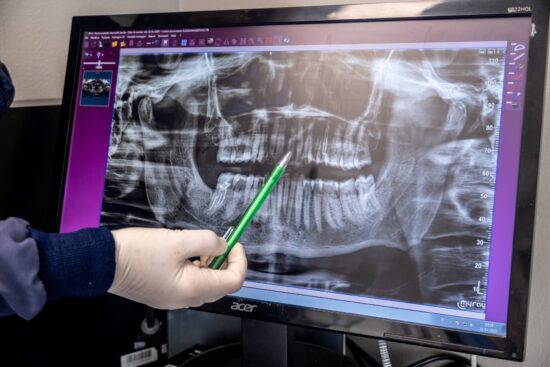

La Dottoressa Stefania Lazzaroni ti illustrerà quale soluzione è perfetta per te, eseguendo una valutazione diagnostica ad hoc con una strumentazione di prim’ordine: Radiografie Endorali , Panoramiche Dentali e Radiologia 2D e 3D.